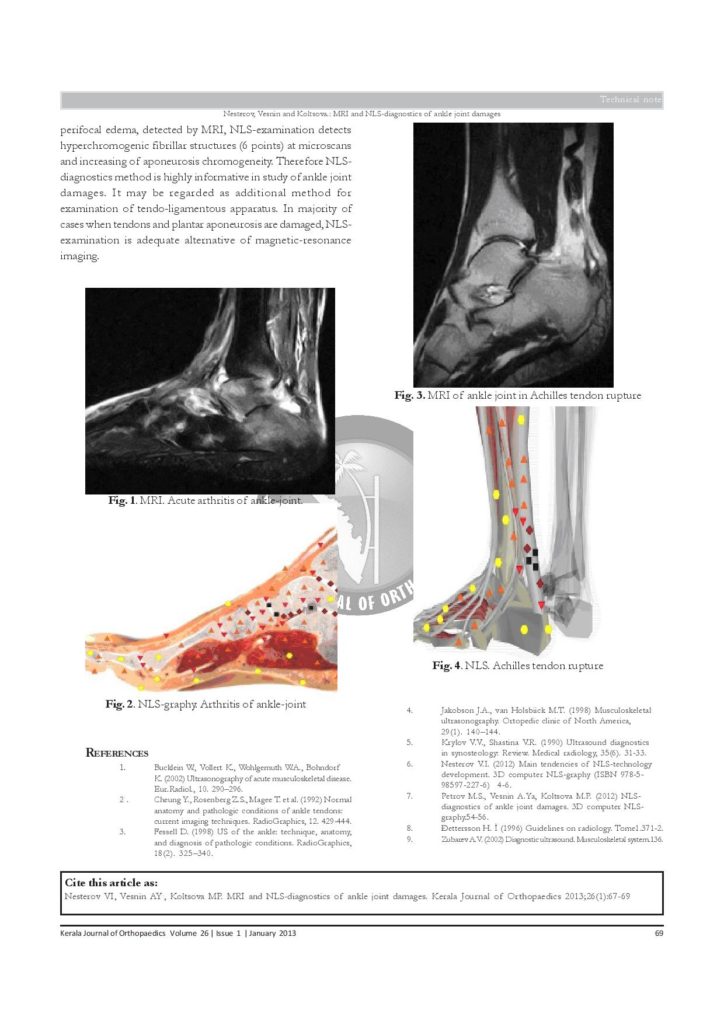

Diagnostyka MRI i NLS uszkodzenia stawu skokowego